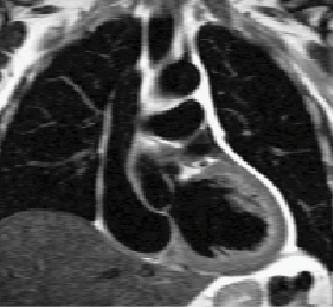

| Filling: | Ejection: | Analysis of properties of blood flow: |